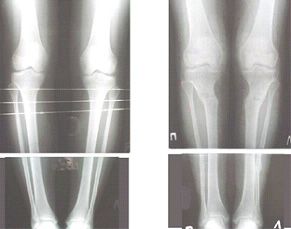

Картинки - в приложении.Будут вопросы - готов ответить.

Ещё картинка - схема. Хотя у Соломина всё написано.

|

Вот ещё картинки, которые отправлял в Ортопод. Коррекция кривизны и удлинение на 3 см.